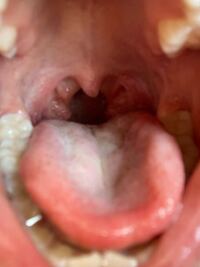

汚くてすみません 片側の扁桃腺だけ大きくこのような形になっています yahoo 知恵袋

子供の扁桃腺です 4歳です ふと見たら大きいと思ったのですが正常ですか yahoo 知恵袋